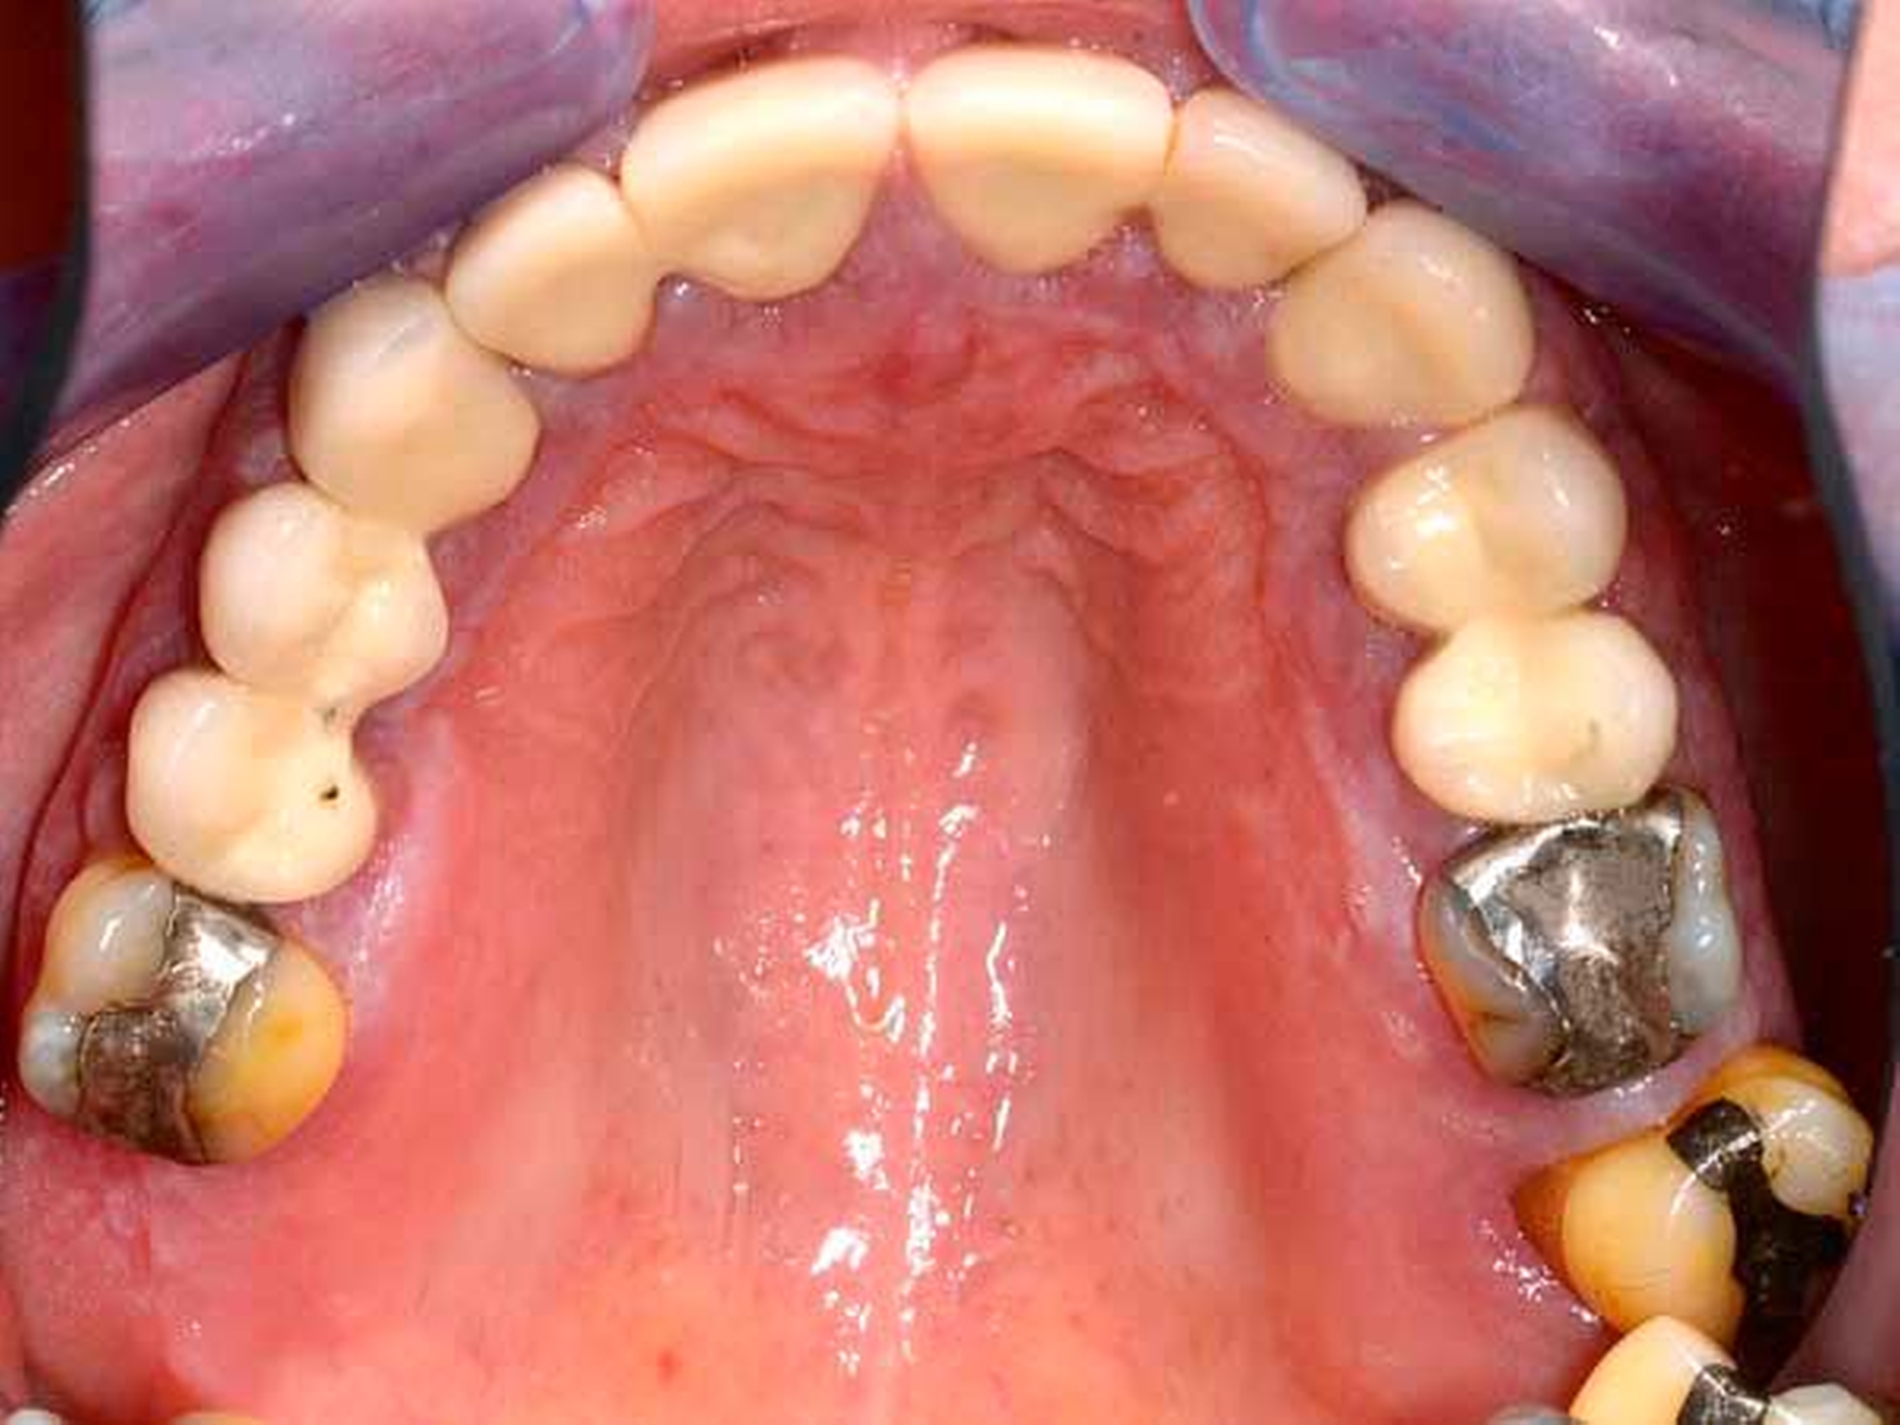

Der Plaqueindex PCR betrug 72 Prozent [O`Leary TJ et al., 1972] und der gingivale Blutungsindex GBI 75 Prozent [Ainamo J et al., 1975]. Das alio loco angefertigte Orthopantomogramm (Abbildung 3) zeigte horizontalen Knochenabbau bis zu einem Drittel der Wurzellänge in beiden Kiefern. Die Zähne 16 und 26 wiesen einen Knochenabbau > 2/3 der Wurzellänge auf. Am Zahn 27 mesial erreichte der Knochenabbau die Wurzelspitze; zudem war der Zahn elongiert und wies eine Kippung nach distal auf. In einer ersten Einzelzahnprognose wurden alle Zähne mit Ausnahme von Zahn 27 als sicher eingestuft. Prothetisch war die Patientin im OK mit einer Brücke (13 bis 15), Kronenblöcken (21/11, 21/22, 24/25) und Amalgamfüllungen an den Zähnen 16 und 26 sowie im UK mit einer geschiebeverankerten Modellgussprothese versorgt.

Neben der Medikamentensubstitution gilt die Plaque- und Entzündungskontrolle als vorrangig therapeutisch beeinflussbar [Lederman D et al., 1984; Seymour RA et al., 2000, Seymour RA, 2006; Thomas DW et al., 2000]. Hierzu zählen Plaque- und Zahnsteinentfernung sowie die Korrektur von Plaqueretentionsstellen. Diese Maßnahmen wurden im dargestellten Fall intensiv durchgeführt. Durch die multiplen Überkronungen lagen zahlreiche subgingival gestaltete und überkonturierte Kronenränder sowie Kronenverblockungen als begünstigende Plaqueretentionsstellen vor. Diese waren jedoch nicht mit einem vertretbaren Aufwand korrigierbar. Adjunktiv zur mechanischen Therapie wurde Chlorhexidingel zur chemischen Belagskontrolle eingesetzt. Auf die kontrovers diskutierte Gabe von Antibiotika wurde verzichtet [Thomas DW et al., 2006].